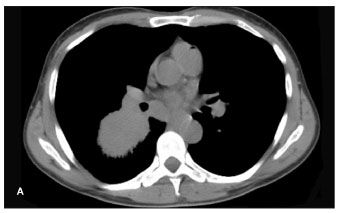

Figure 1. Chest CT scan showing a right infrahilar mass (A) and head CT scan showing brain metastases in a 58-year-old, HIV-infected male smoker in whom small-cell lung cancer was diagnosed.

Compared with their HIV-negative counterparts, HIV-positive patients with lung cancer are younger at diagnosis (45 vs 62 years) and have a worse prognosis, regardless of whether or not they are receiving antiretroviral therapy.46-49 One-year survival rates for HIV-positive patients are about 10%, compared with 40% for HIV-negative patients, and fewer HIV-positive patients than HIV-negative patients are alive after 2 years.46-49 There is no difference in the types of lung cancer diagnosed in HIV-positive patients and those diagnosed in age-matched controls, with non-small-cell cancer being the most common.46